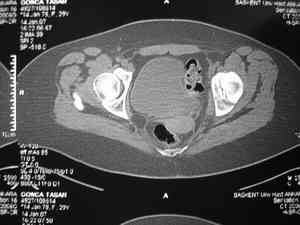

Dear group,30 years age female MVA front seat, head trauma + post column left acetabular fracture, 2.5 weeks skeletal traction. She is now conscious but still confused without any surgical treatment for brain edema.

Latest X rays and CAT is attached.Fracture within first 1.5 cm from the weight bearing dome, although AP and Obtrator oblique good, iliac oblique view reveals some displacement.I'm not sure that nonsurgical treatment will be OKHüseyin DemirorsBaskent UniversityDept of Orthopedics and TravmatologyAnkara TURKEY

My vote, given the amount of displacement on the iliac oblique and CT scan, would be for ORIF thru a posterior approach ASAP - these get pretty tough

I may get beat up for this, but I see very little displacement that concerns me on the CT. The radiograph is more concerning. I suspect it could look better, and the gap made smaller on CT. Not sure if it will affect outcome. I might give it a shot and try to see what could be done.